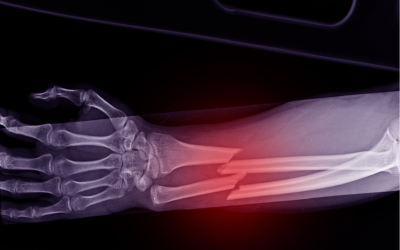

This CME series provides a focused exploration of musculoskeletal conditions in children, emphasizing the unique principles that guide diagnosis and management in paediatric orthopaedics. Participants will gain insights into the principles of fractures in children, common fracture patterns, and the clinical approach to the limping child, as well as an understanding of metabolic bone conditions affecting growth and development. The series equips healthcare professionals with practical knowledge to enhance early detection, effective treatment, and long-term care for paediatric patients.